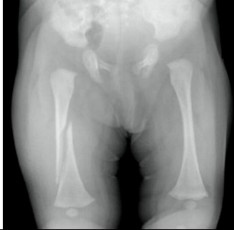

A 6-week-old infant is brought to your clinic with a swollen left thigh. The baby has been irritable for the last two days especially with diaper changes. You obtain the following radiograph.

What is the most likely diagnosis/etiology?

Femur fracture – likely inflicted injury (child abuse) but also consider OIIn addition to appropriate medical therapy, what else needs to be done at this point?

Notify MSW, CPS (DCS), law enforcement -

A 6-week-old infant is brought to your clinic with a swollen left thigh. The baby has been irritable for the last two days especially with diaper changes. You obtain the following radiograph. After gathering a history from the caretakers, there is no known mechanism to explain the injury.

What other radiographic studies are recommended in this context to screen for occult injuries (be specific)?

Skeletal Survey and Head CTIn addition to medical therapy, what else needs to be done at this point?

Notify social work, CPS (DCS), and law enforcement. Call CPS must be included to get credit. -